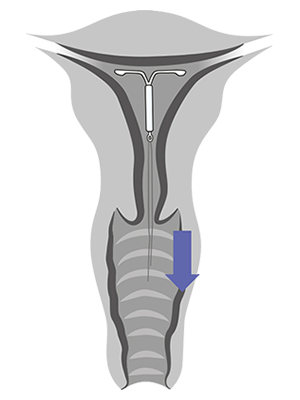

Ta ut eller bytte av Kyleena i noen få enkle trinn

Se hvordan du tar ut Kyleena

Kyleena tas ut ved å trekke forsiktig i trådene med en tang.

Hvis trådene ikke er synlige og systemet viser seg å være i livmorhulen ved bruk av ultralyd, kan den tas ut ved bruk av en smal tang.

Det kan være nødvendig med dilatasjon av cervikalkanalen eller kirurgisk inngrep.

3 trinn for riktig uttak av Kyleena

Hormonspiralen skal tas ut innen utgangen av det femte året

Hvis kvinnen ønsker å bruke den samme metoden, kan ny hormonspiral føres inn umiddelbart etter uttak.

Hvis graviditet ikke er ønskelig, skal uttak utføres innen 7 dager etter første menstruasjonsdag, gitt at kvinnen fremdeles har en regelmessig menstruasjonssyklus.

Hvis hormonspiralen tas ut på et annet tidspunkt i løpet av syklusen, eller hvis kvinnen ikke har en regelmessig menstruasjonssyklus og kvinnen har hatt samleie den siste uken, kan hun være gravid.

For å sikre kontinuerlig prevensjon bør en ny hormonspiral føres umiddelbart inn, eller en annen prevensjonsmetode bør igangsettes.